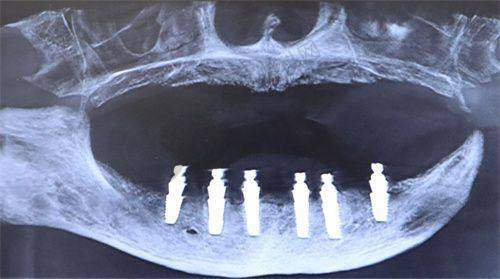

陕西省人民医院口腔科可开展全口数字化种植、ONLY 植骨术、骨劈开术、GBR 手术、即刻种植、上颌窦外提升等高难度的种植技术。

西安交通大学医学校第一附属医院口腔科引入机器人种植(5 分钟/颗)、3D 导板设计,减少人力与耗材浪费;提供3D 数字化模拟矫正方案,提前预览牙齿移动轨迹。

西安瑞泰口腔医院配备数字化等设备,确保诊疗过程的精细与安心,开展种植牙、牙齿矫正等特色项目。